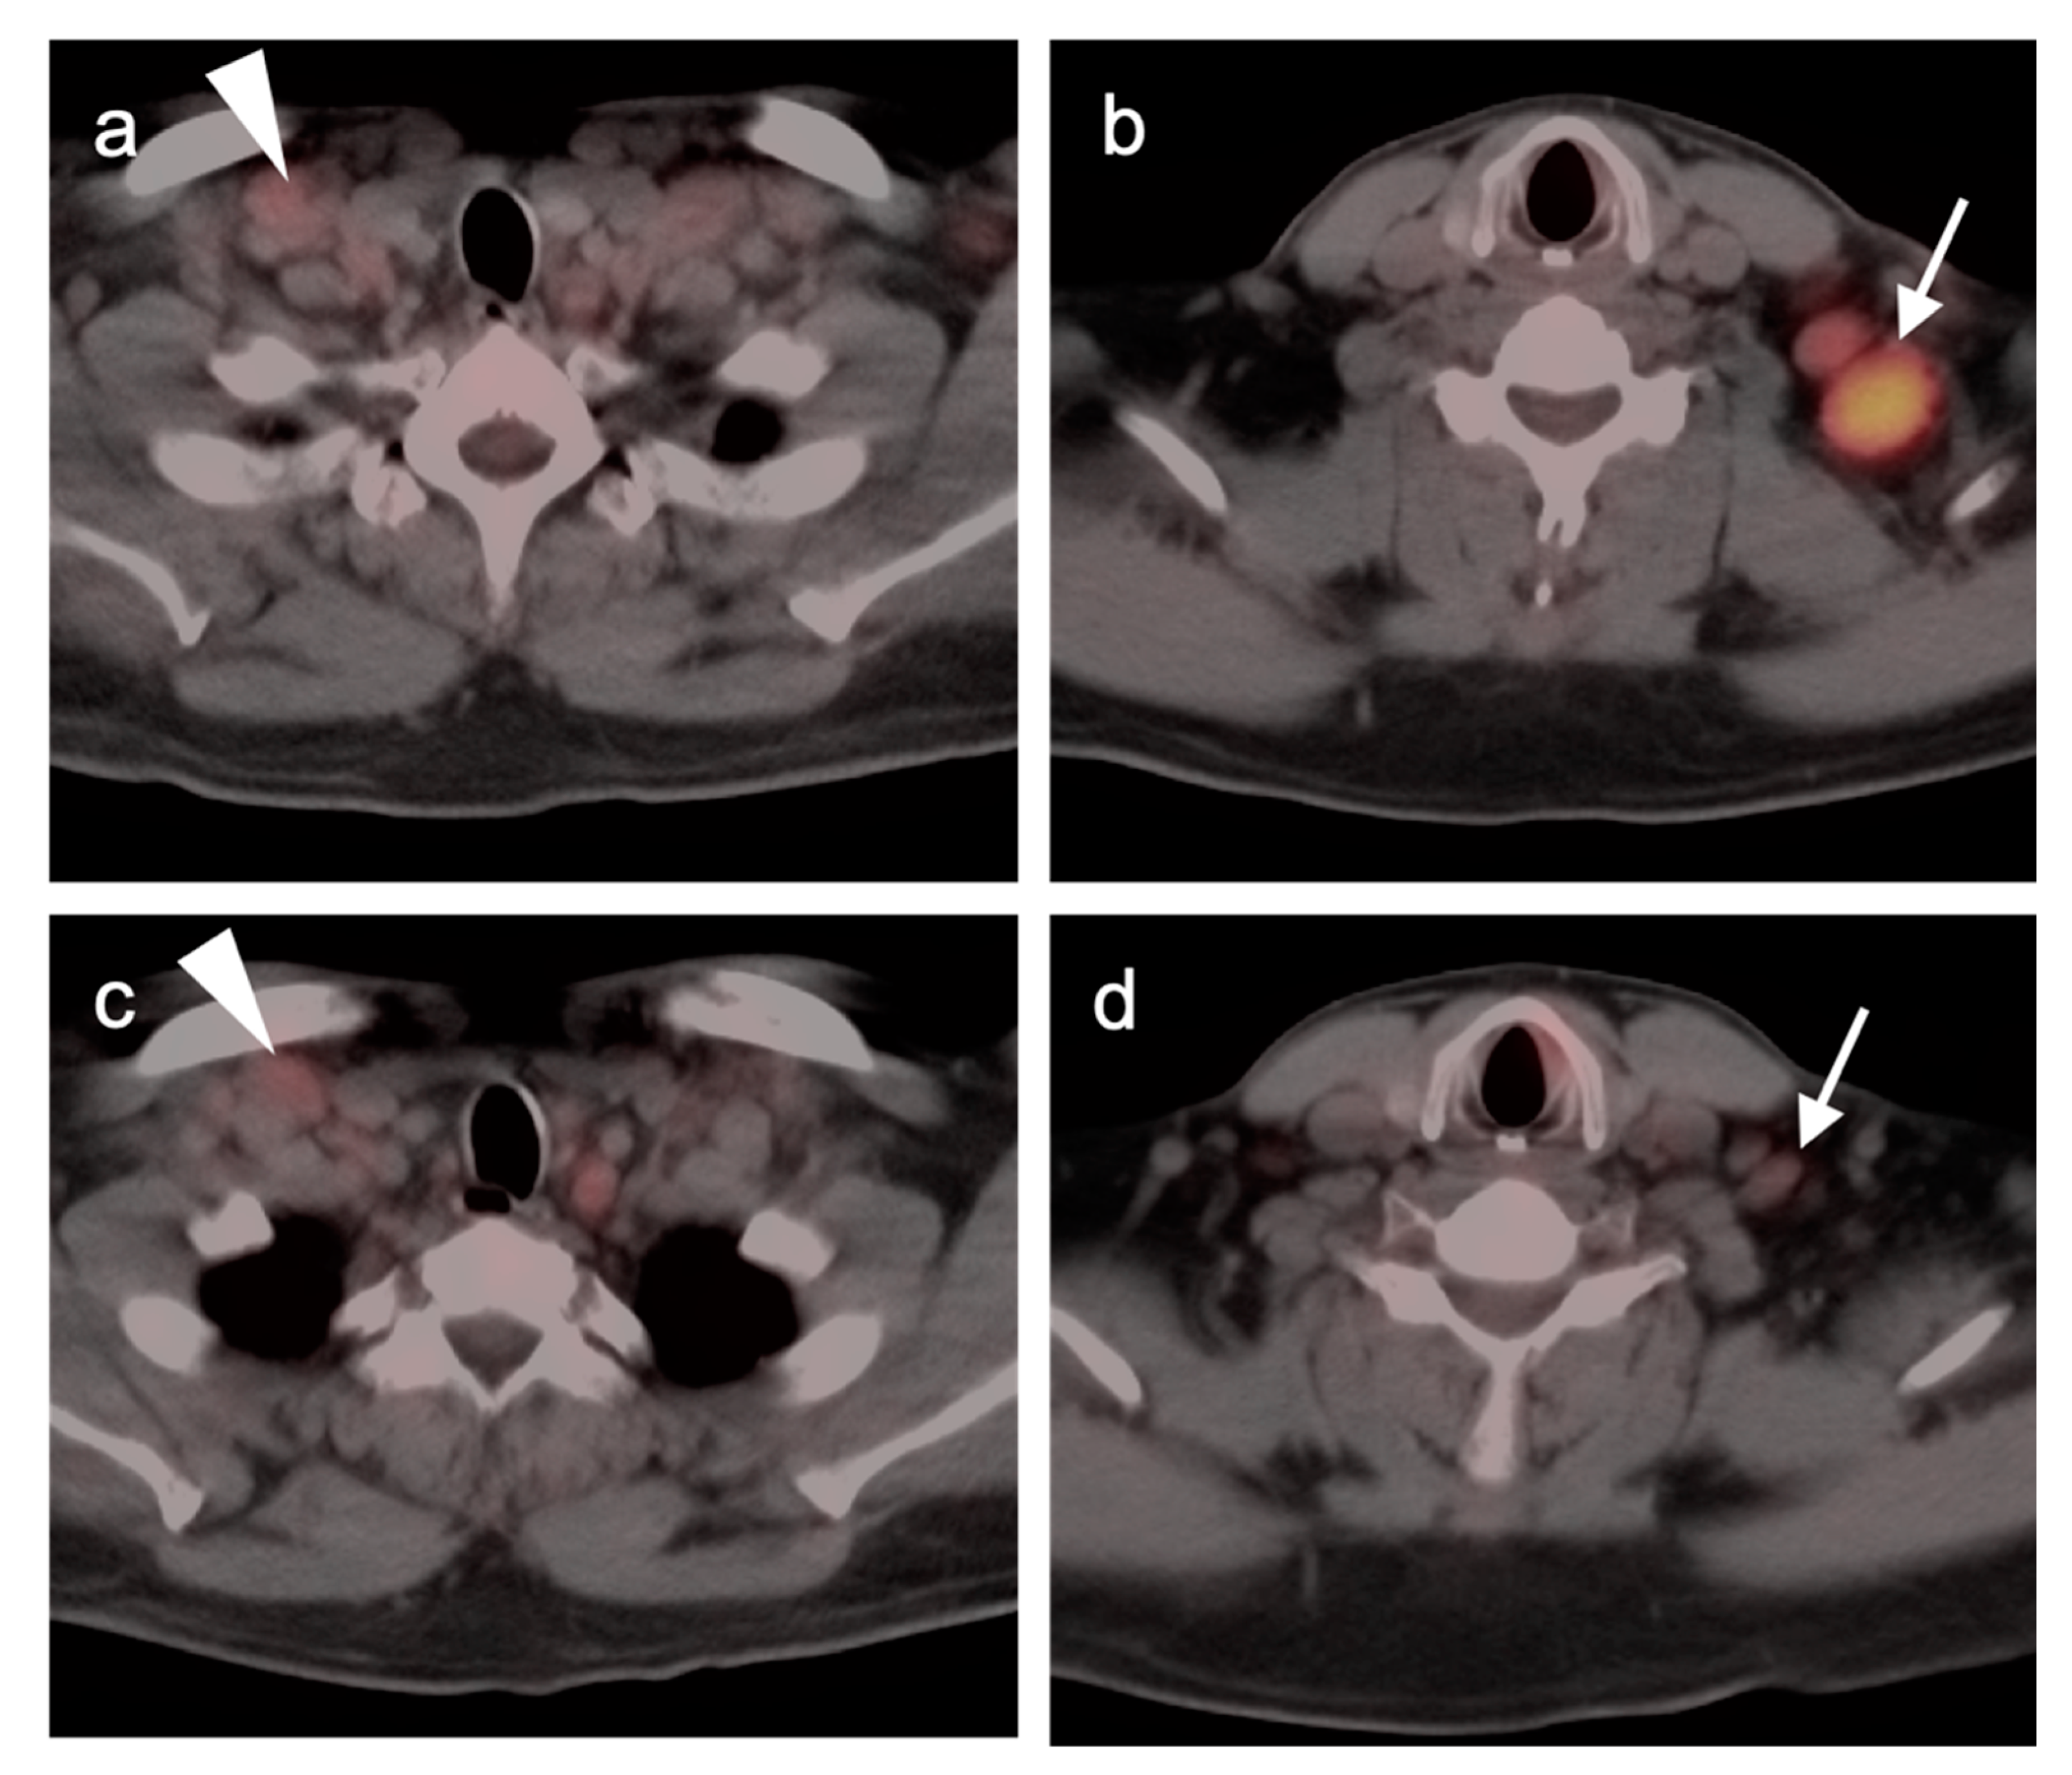

2.2.3. Baseline FDG PET-CT for Staging Lymphoma

- Kashyap, R.; Rai Mittal, B.; Manohar, K.; Balasubramanian Harisankar, C.N.; Bhattacharya, A.; Singh, B.; Malhotra, P.; Varma, S. Extranodal manifestations of lymphoma on [¹⁸F]FDG-PET/CT: A pictorial essay. Cancer Imaging 2011, 11, 166–174. [Google Scholar] [CrossRef]

2.5. T-Cell Lymphoma (TCL)